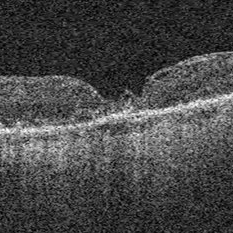

Stage 2 Macular Hole From VMT

Stage 2 Macular Hole From VMT

Mar 21 2025 by Drew Mitchell

HD 1 line 100x OCT showcasing a full thickness macular hole caused by vitreomacular traction on fovea. Choroidal folds can also be seen on scan.

Photographer: Drew Mitchell OCT-C

Imaging device: Zeiss Cirrus 6000

Condition/keywords: Choroidal Folds, FTMH, macular hole, OCT, PVD